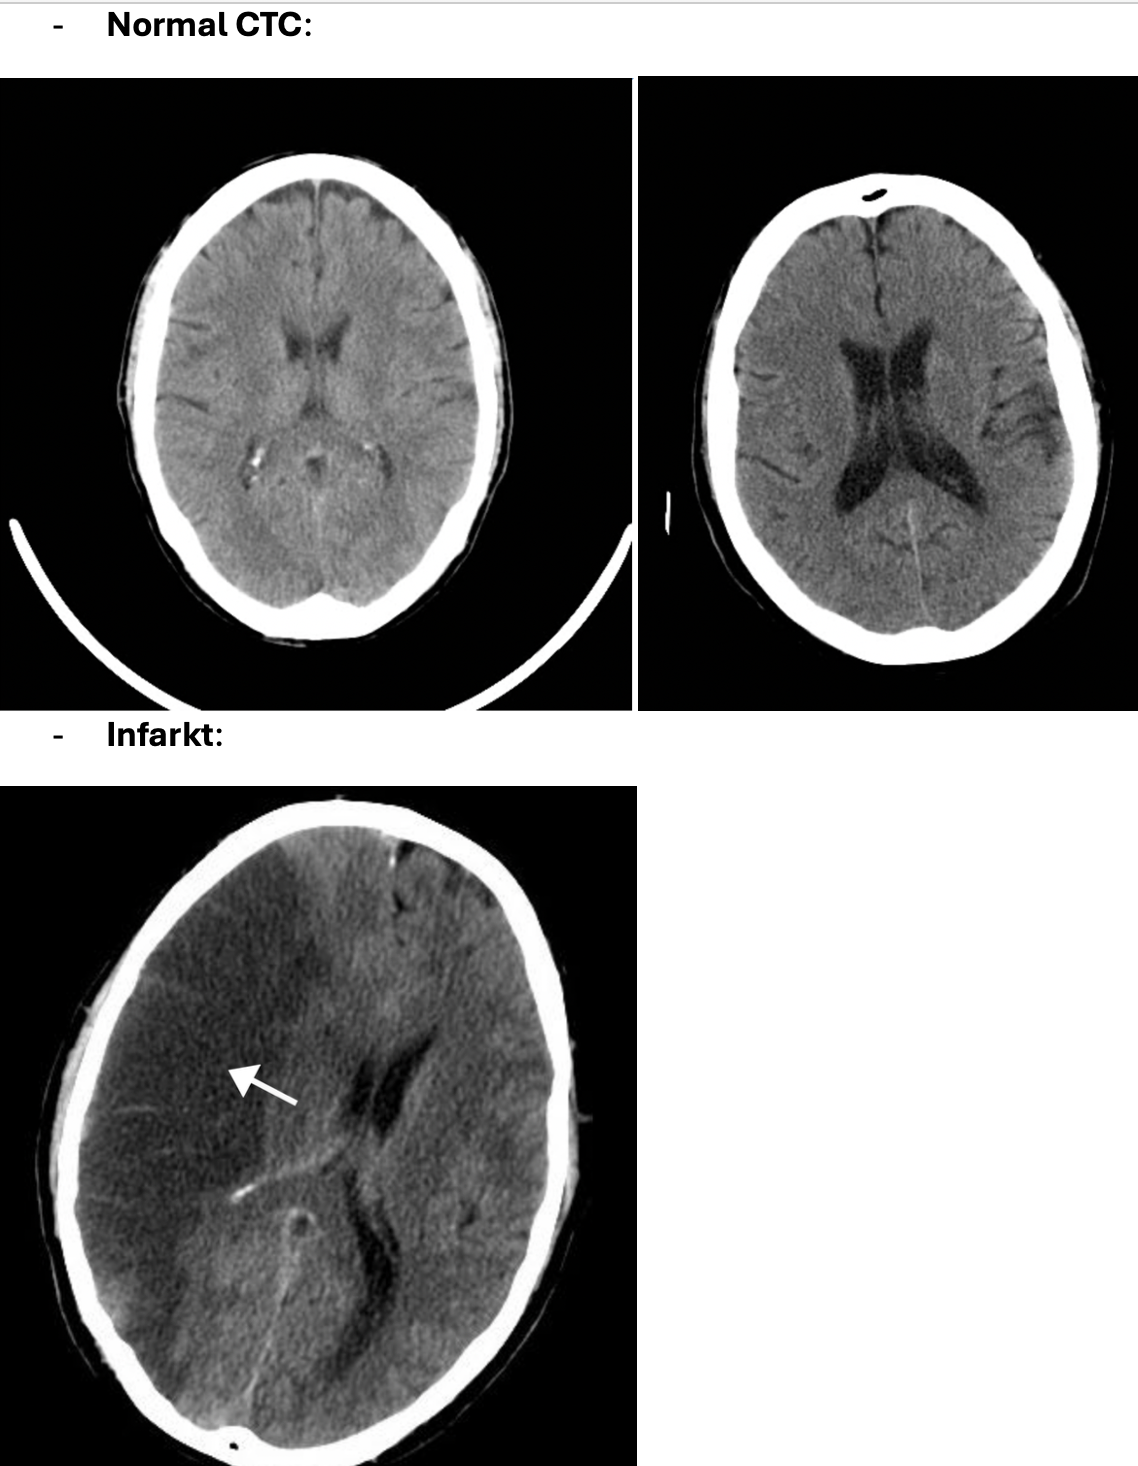

Infarkt (apopleksi/TCI):

A

Diagnose?

Infarkt (apopleksi/TCI)